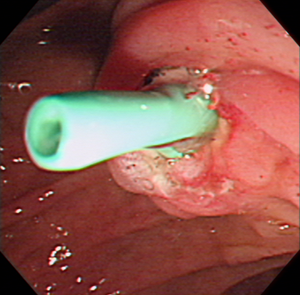

첫째는 특수 제작된 내시경(십이지장경)을 식도, 위를 거쳐서 십이지장 제 2부까지 유치시키고, 췌-담관이 십이지장으로 개구되는 유두부를 찾아서 육안으로 관찰하고, 카테터(가느다란 관)를 내시경 내의 작업관을 통해 췌관 혹은 담관으로 삽관한다.

둘째는 삽관된 카테터로 방사선 조영제를 주입하여 담관 또는 췌관에 대해 방사선 투시 및 촬영을 하여 진단을 하고 필요하면 유두부를 절개하여 담관-췌관의 병을 치료하는 것이다. 이런 시술을 내시경 역행성 담도-췌관 조영술(ERCP)이라고 한다. 즉, 이 검사는 내시경 검사와 방사선 검사 둘 다를 포함한다. 따라서 ERCP를 시술하는 의사는 내시경 술기와 투시 조영술 모두에 전문가이어야 한다. 또한 ERCP를 이용한 중재적 시술은 상부소화관내시경 검사보다 시간이 더 걸리고 중증의 합병증 위험이 있어서 모든 내시경의사가 ERCP를 할 수는 없고 전문적인 수련 과정을 이수한 후에 시술을 하는 것이 바람직하다.